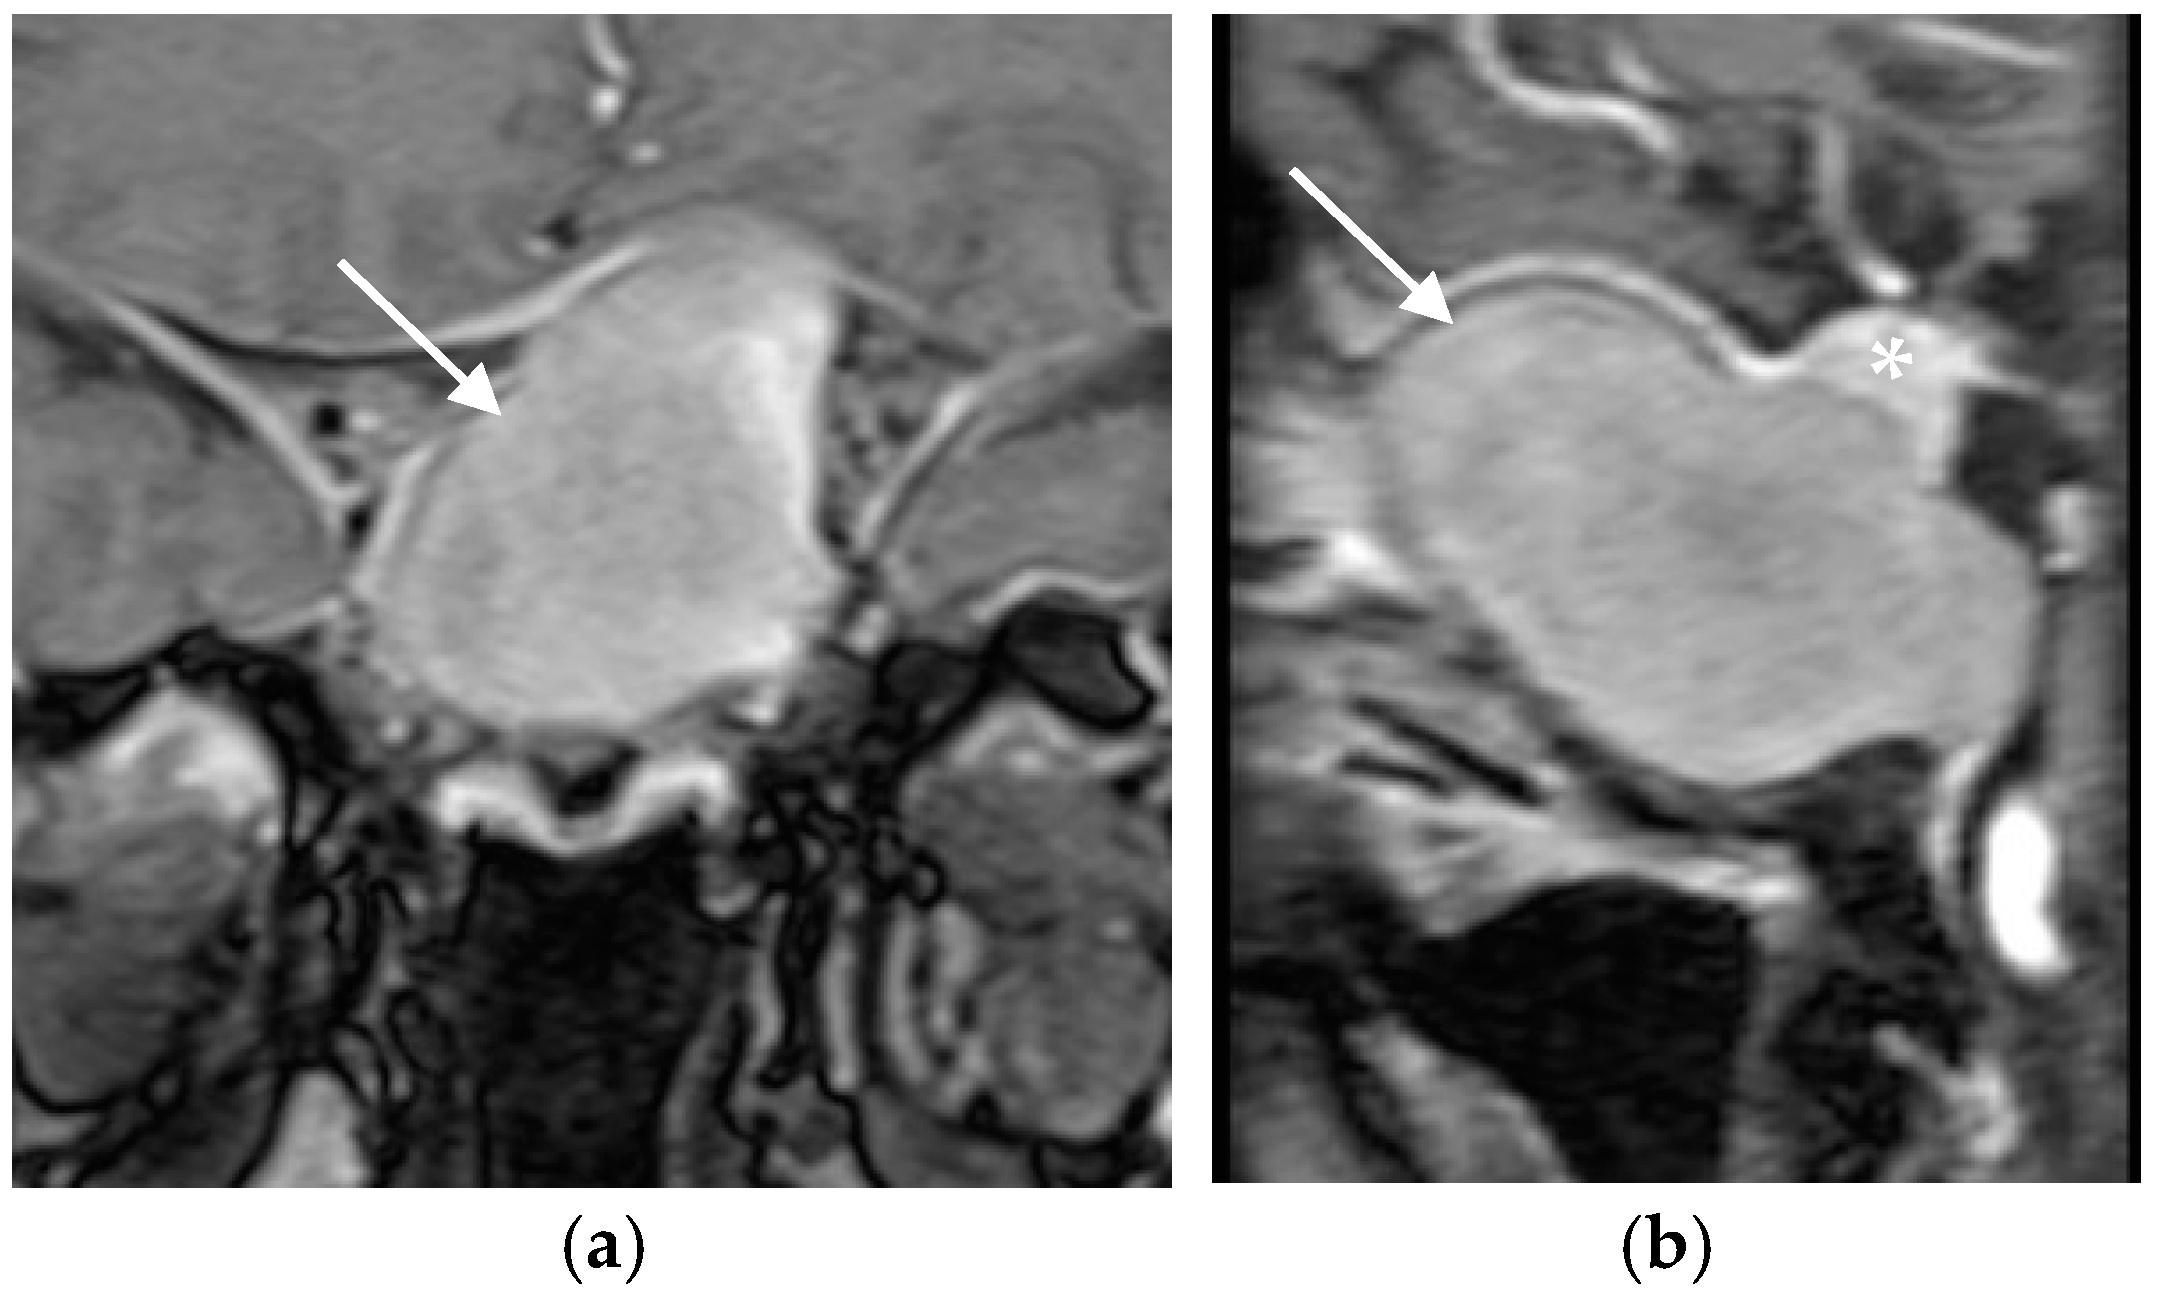

3.1. Case Presentation

3.3. Surgical and Pathological Findings